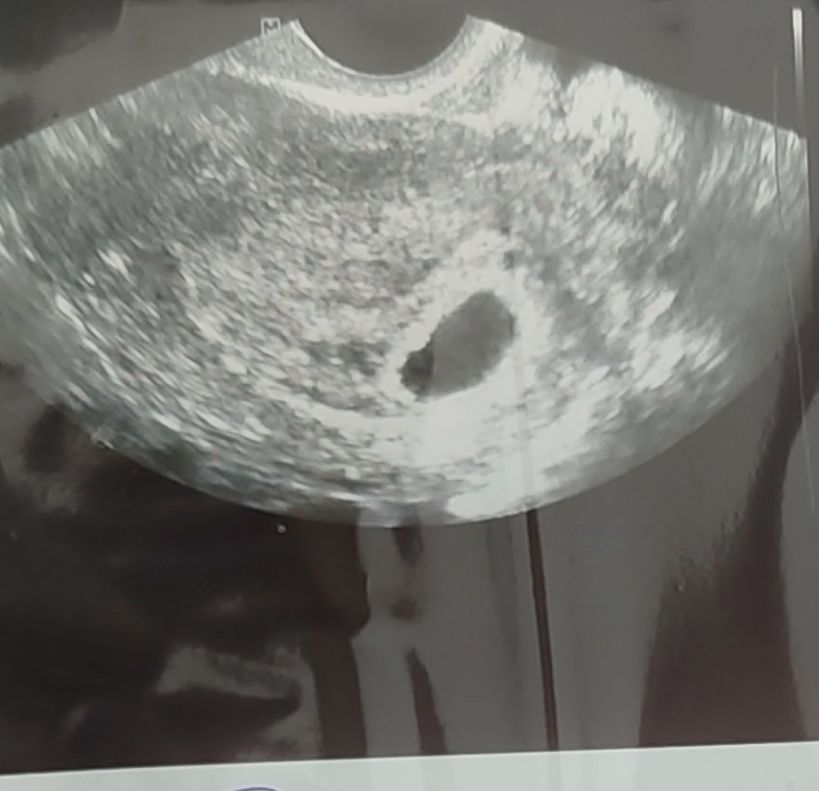

Узи , желточный мешок

У меня в 5 недель тоже просто черное пятнышко было пустое, в 7 уже и эмбриончик и сердечко)

Аля, на картинке нет (в дневнике есть фото), на узи в описании было. Но иногда не видят, если срок маленький.

Аля, ну я ж вам и говорю, у меня жм на фотке не было, просто черное пятнышко, но в описании к узи было. Но у вас могли просто не увидеть пока, может рано еще.

Анастасия , посмотрела. Вам то написали, что у вас есть ж.м. Надеюсь, что УЗИстка просто дура. Сначала сказала ,ой вижу жм,а потом " а нет, это не он"((( реву весь день

Анастасия , мой репродуктолог 30 числа поставила срок по дате переноса - 4 нед. По дате месячных сегодня 5 нед и 5 дней... А по переносу сегодня - 4 нед и 4 дня А узиска написала 5 нед. 🤦🏼‍♀️